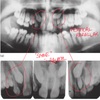

What is this showing?

Overjet (horizontal overlap of the teeth)

29

Overbite (vertical overlap - the distance between the upper front teeth covering over the lower front teeth)